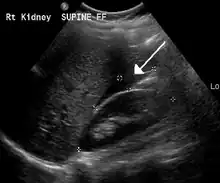

Transvaginal ultrasonography of an ectopic pregnancy, showing the field of view in the following image.

A "blob sign", which consists of the ectopic pregnancy. The ovary is distinguished from it by having follicles, whereof one is visible in the field. This patient had an intrauterine device (IUD) with progestogen, whose cross-section is visible in the field, leaving an ultrasound shadow distally to it.